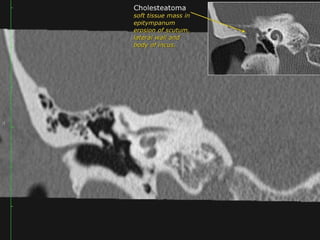

Acquired Cholesteatoma :

39 year old F with left conductive hearing loss.

Click to Return to Algorithm

A: CT Rt axial

B: CT Rt cor

C: CT Lft axial

D: CT Lft cor

Normal

Scutum

Soft tissue density within the

middle ear cavity. It

obliterates Prussak’s space

and erodes the scutum and

ossicles.

Clear

Middle

ear

cavity